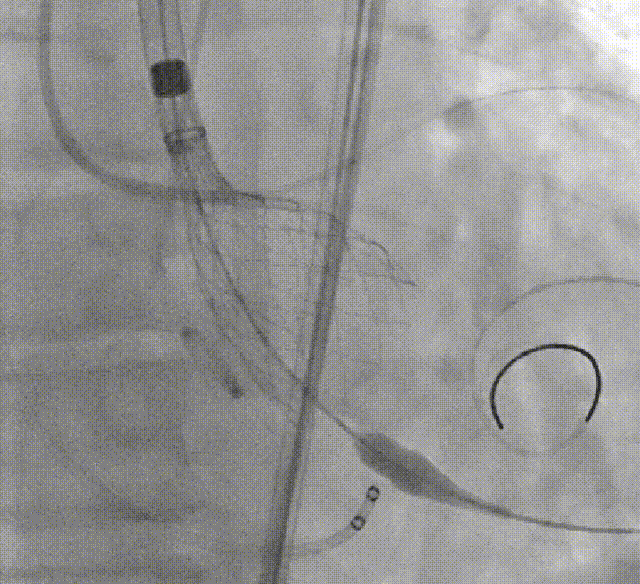

术者采用患者右侧主入路,顺利完成导丝和猪尾跨瓣等准备工作。进Landerquist超硬导丝,采用25mm球囊进行预扩,仔细评估冠脉风险后,决定对冠脉采取保护措施。根据球囊扩张情况,术中决定使用金仕生物的ProStyle预装干瓣TAV32。打开包装后,很迅速的完成了瓣膜和系统植入前的准备。输送过程系统和瓣膜轻松过弓并顺利跨瓣;开始初步释放,然后快速起搏下释放,发现位置略高后进行回收,重新定位后最终成功完成释放。反复造影发现冠脉存在阻塞风险,武汉协和团队按照风险预案在左冠植入4.0*18mm支架进行保护。术后显示左右冠脉血液灌注通畅,术后超声测量峰值流速1.45m/s,峰值压差8mmHg,几乎无瓣周漏。入路闭合顺利,无心脏及血管并发症,手术成功。

球囊扩张

初步释放

再回收后释放,术中冠脉评估

系统撤出

支架植入